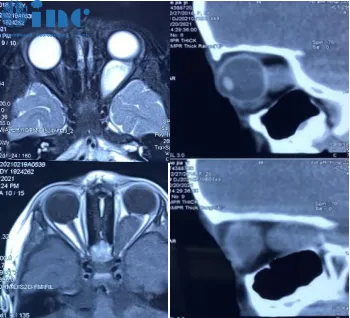

患者为一名3岁儿童,名为糖糖,诊断为左侧视神经胶质瘤。

2021年2月,患儿父母发现孩子左眼存在轻微外突表现,前往医院检查后确诊为左眼占位性病变。另一家医院的诊断结果为血管瘤,患儿住院治疗约十余天,医生给出的建议是采取保守治疗。

2021年6月,家属再次前往当地眼科医院咨询,医生明确诊断为视神经胶质瘤,并建议尽快实施手术切除肿瘤,但同时也告知术后左眼将完全失明。同月,患儿辗转至其他医院,完成系列检查后,医生建议先行化疗。由于当时糖糖眼球外突症状尚不严重,父母最终选择了观察等待的保守治疗策略。

2021年11月,父母观察到孩子的左眼球外突程度持续加重,视力相较于发病初期也出现显著下降,目前左眼仅存光感。

诊断非常明确,为左侧视神经胶质瘤。

最合适的治疗方案是手术全切肿瘤性视神经的最远端与最近端部分,以防止肿瘤向对侧扩散。即使患者左眼可能仍保留部分残余视力(但以如此大小的肿瘤来看,左眼很可能已经失明),也必须将神经完全离断,否则肿瘤可能继续向视交叉生长,最终侵犯健康的右侧视神经。这无疑是必须全力避免的情况。

从发现肿瘤至今的这段时间,在未接受任何治疗的情况下,患儿视力呈现进行性丧失,因此高度怀疑为一种进展性的视神经胶质瘤。若该诊断得到确认,则需要进行手术切除。肿瘤的进展情况也应通过对系列磁共振成像研究的精确评估来验证。然而,在决定进行手术切除之前,仍有时间尝试化疗治疗。我们应在2-3个月后验证化疗在控制肿瘤生长方面的有效性。若该治疗失败,则应考虑进行手术切除。

肿瘤的切除应力求完整。部分切除已被证实无法控制肿瘤生长,并且几乎总是与术后视力恶化或失明相关。